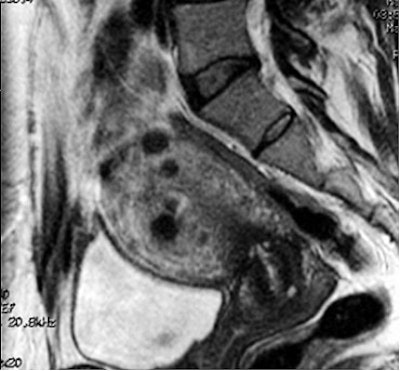

![]() |

| This pre-embolization, sagittal T1-weighted midline MR depicts an enlarged uterus with multiple fibroids highlighted by white arrows. The black arrow points out the uterus impinging anteriorly on the bladder neck. Image courtesy of Dr. Steven Janney Smith. |